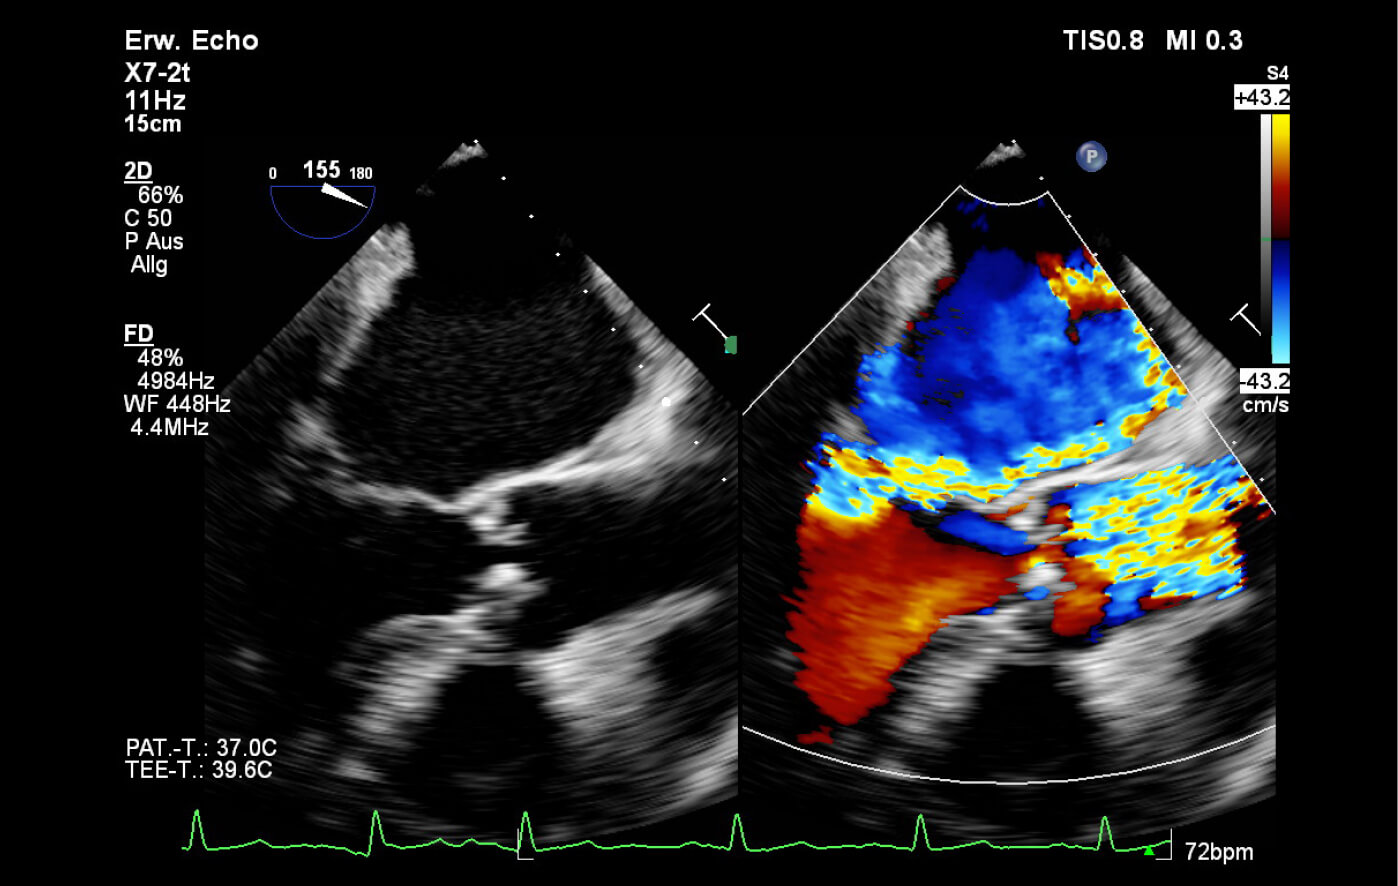

Die Transösophageale Echokardiographie (TEE) ist eine spezielle Form des Herzultraschalls, bei der eine schlanke Ultraschallsonde in die Speiseröhre eingeführt wird. Da sich die Speiseröhre anatomisch direkt hinter dem Herzen befindet, lassen sich so besonders hochauflösende Bilder der Herzklappen, der Vorhöfe und der großen Gefäße

gewinnen, die durch die konventionelle Echokardiographie von außen nicht erreichbar sind.

Die TEE wird eingesetzt bei Verdacht auf Blutgerinnsel im Herzen, bei Herzklappenentzündungen (Endokarditis) oder zur exakten Beurteilung von Herzklappenfehlern vor Operationen oder Kathetereingriffen. Die Untersuchung erfolgt in örtlicher Betäubung des Rachens. In den meisten Fällen kann die Untersuchung so in unseren Praxisräumen erfolgen. Bei Bedarf wird die Untersuchung in Kooperation mit dem Klinikum Dritter Orden mit einer leichten Sedierung organisiert.